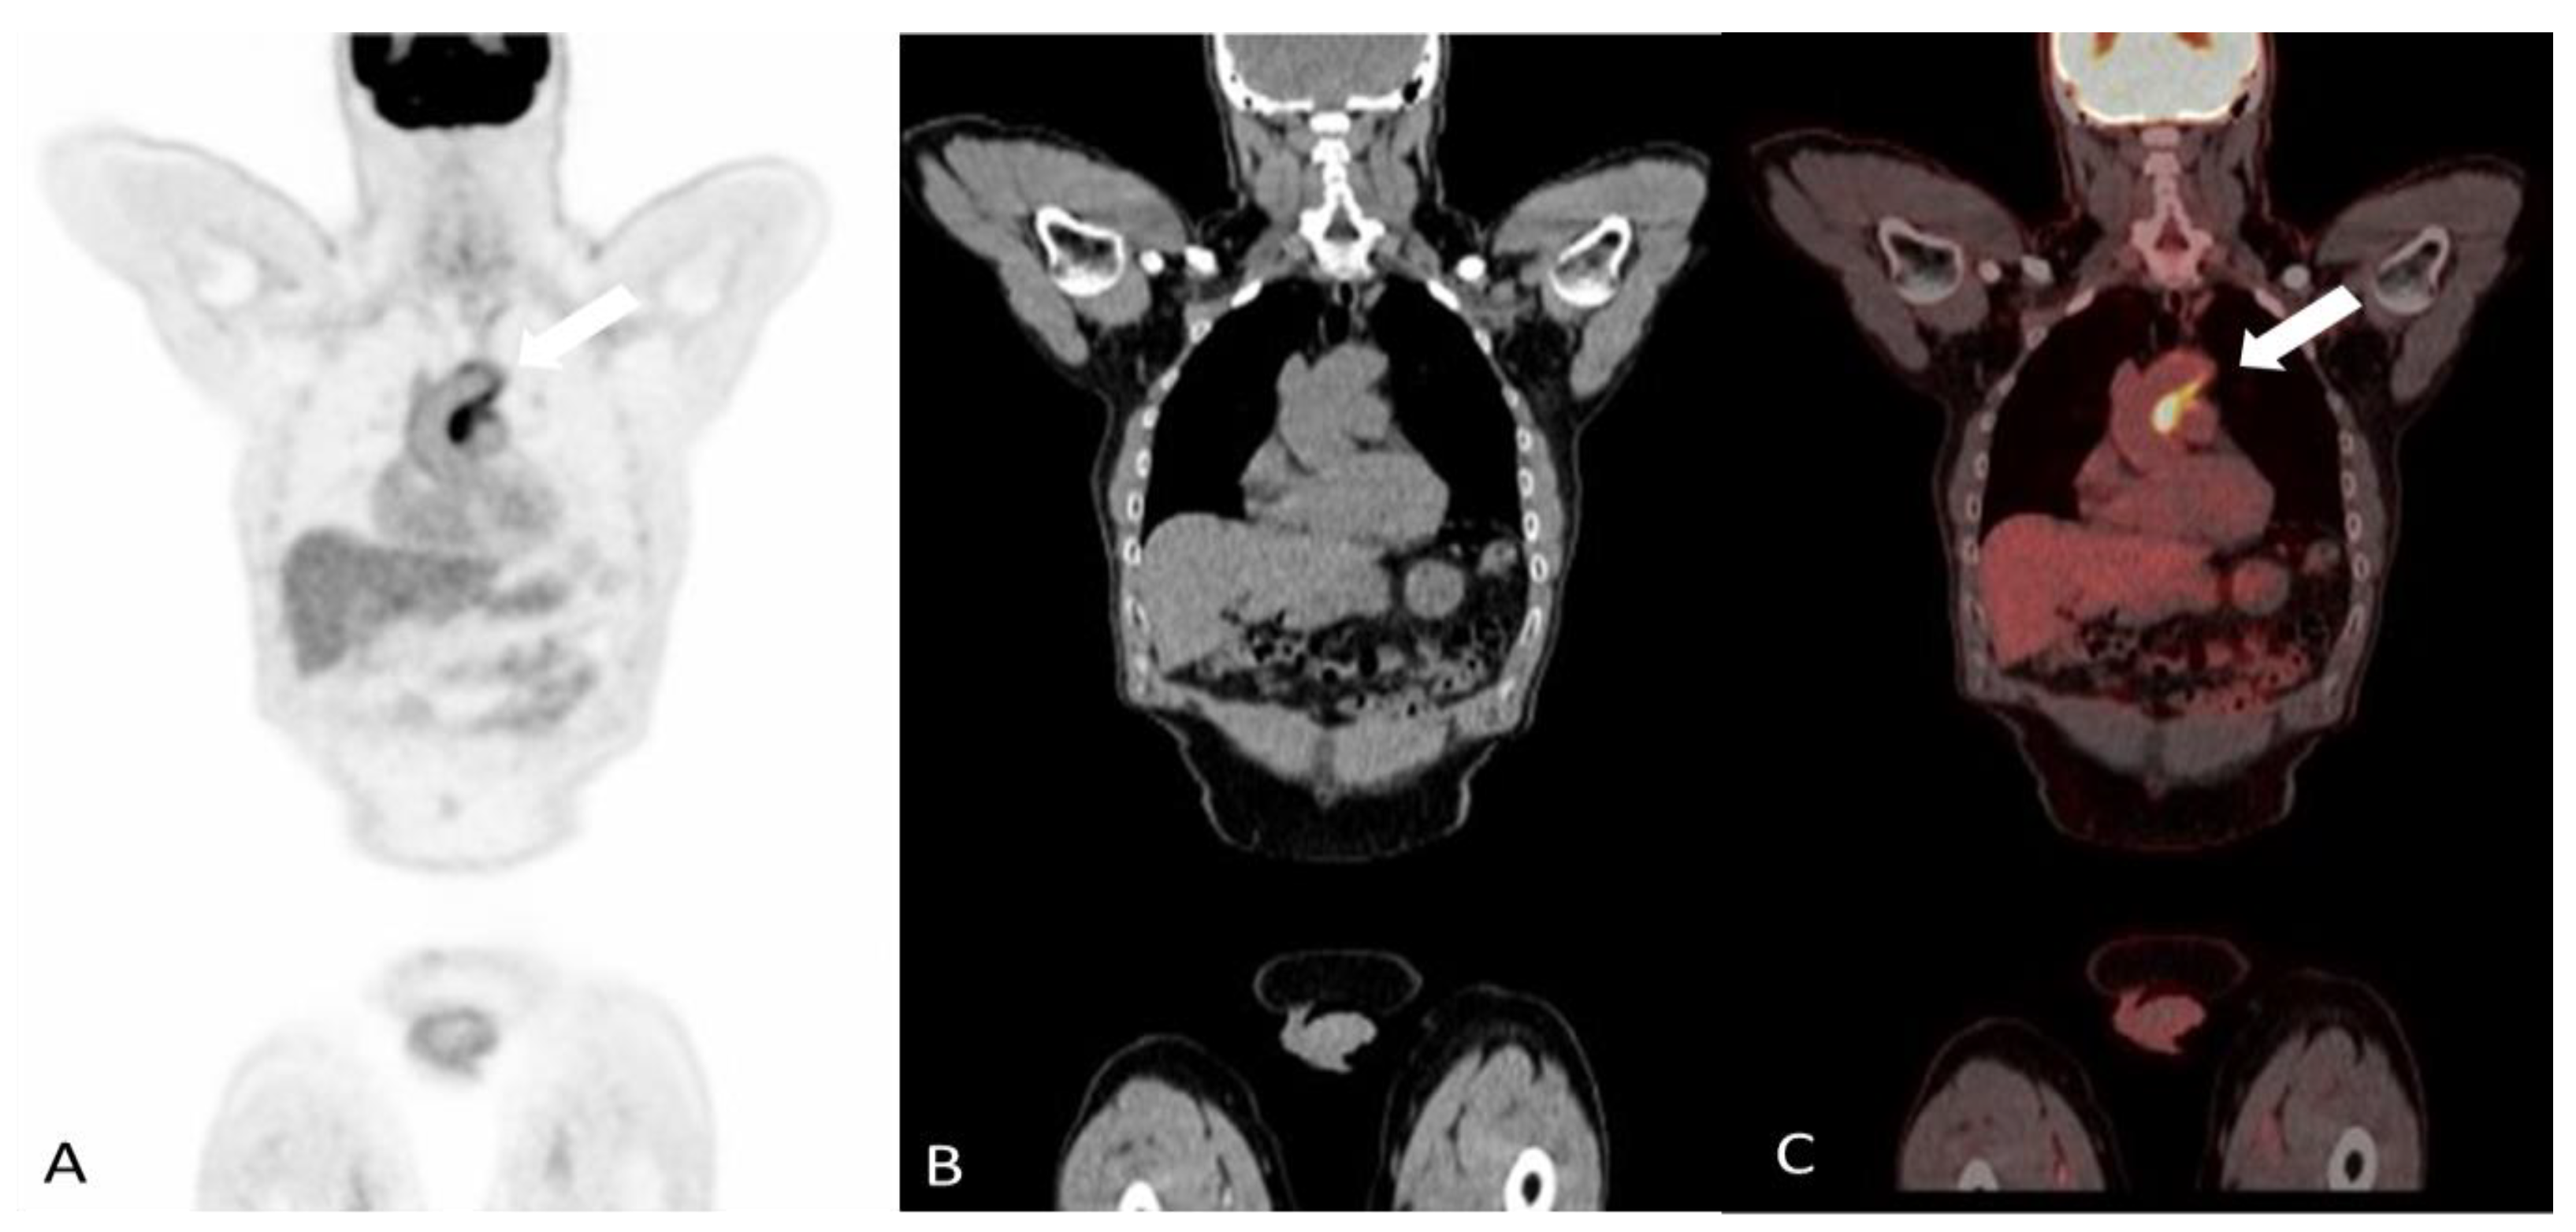

- Soussan, M.; Abisror, N.; Abad, S.; Nunes, H.; Terrier, B.; Pop, G.; Eder, V.; Valeyre, D.; Sberro-Soussan, R.; Guillevin, L.; et al. FDG-PET/CT in patients with ANCA-associated vasculitis: Case-series and literature review. Autoimmun. Rev. 2014, 13, 125–131. [Google Scholar] [CrossRef]

- Kemna, M.J.; Vandergheynst, F.; Voo, S.; Blocklet, D.; Nguyen, T.; Timmermans, S.; van Paassen, P.; Cogan, E.; van Kroonenburgh, M.; Tervaert, J.W.C. Positron emission tomography scanning in anti-neutrophil cytoplasmic antibodies-associated vasculitis. Medicine 2015, 94, e747. [Google Scholar] [CrossRef] [PubMed]